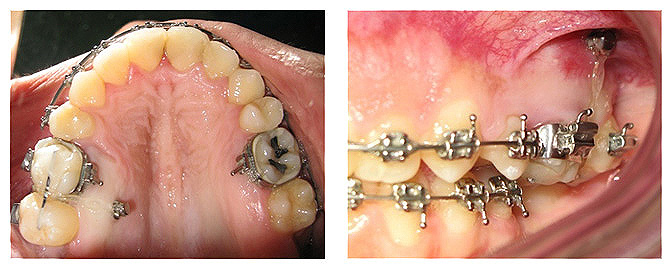

Dente canino não erupcionado e apinhamento dentário.

![]() |

Criação de espaço para tração do dente canino, após 6 meses de tratamento.